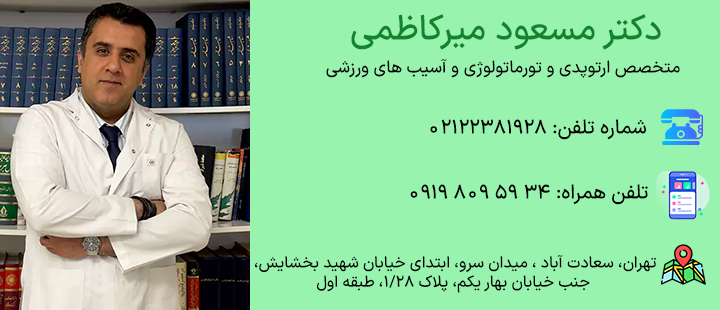

پروتز زانو به منظور بازگرداندن حرکت طبیعی و کاهش درد مزمن طراحی شده است. این روش در بیماران با آسیبهای شدید یا آرتروز پیشرفته نتایج مطلوبی دارد. فرآیند جراحی شامل برداشتن بخش آسیبدیده و نصب پروتز مناسب با آناتومی بیمار است. مراقبتهای پس از عمل شامل کنترل درد، ورزشهای توانبخشی و پیشگیری از عفونت میباشد. رعایت کامل این مراحل موجب افزایش دوام مفصل و عملکرد بهتر زانو در بلند مدت میشود. در ادامه به بررسی این موضوع به کمک دکتر مسعود میرکاظمی متخصص ارتوپدی و تورماتولوژی و آسیب های ورزشی خواهیم پرداخت.

دکتر مسعود میرکاظمی بهترین جراح تعویض مفصل زانو و تورماتولوژی و آسیبهای ورزشی با روشهای پیشرفته، سلامت و عملکرد شما را بهبود میبخشد. برای مشاوره با ایشان با ما همراه باشید.

دکتر مسعود میرکاظمی

برای دریافت نوبت و مشاوره تخصصی با ما در ارتباط باشید.

متخصص ارتوپدی و تورماتولوژی و آسیب های ورزشی

فلوشیپ جراحی تومورهای استخوانی و عضلانی

عضو انجمن بین الملی حفظ اندام امریکا و اروپا ( ISOLS )

عضو انجمن جراحان ارتوپدی ایران ( IOA )

استاد یار دانشگاه